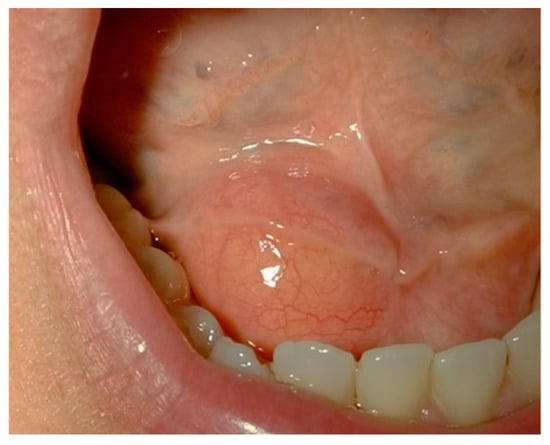

445 nm Blue Laser in Excisional Biopsy of a Large Lipoma of the Mouth Floor †